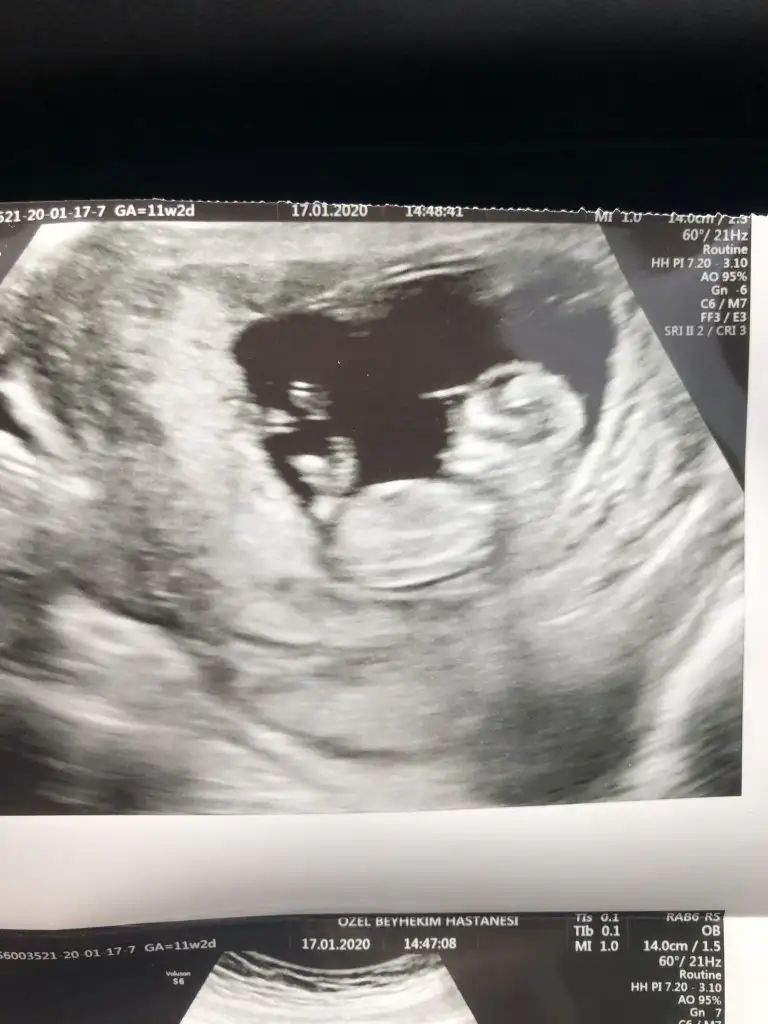

Anket Nub teorosi dogru tahminmi arkadaşlar

Nu teorisi dogrumu yanlışmı

• Tahminim dogrumu

OY: 357 76,6%

• Tahminim yanlışmı

OY: 109 23,4%

• Ankete Katılan

466

Valla dün 15+0 dı doktor hala yüzde yüz kız demedi 80 diyor:) ama zannetmiyorum değişeceğini daha öncede kız gibi demişti başka bi doktor